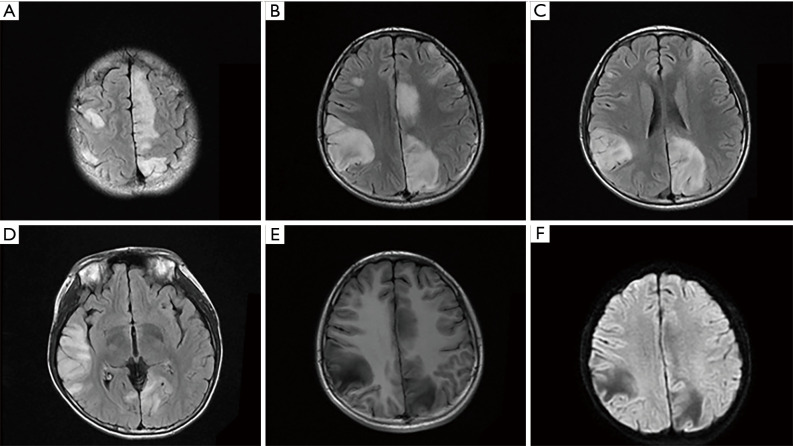

Figure 1. The MRI features of the novel R317S variant. (A-D) The axial FLAIR showed multiple signal abnormalities in bilateral frontal, temporal, parietal occipital lobes. Hypointense lesions were seen on T1-weighted imaging (E) and on DWI (F).